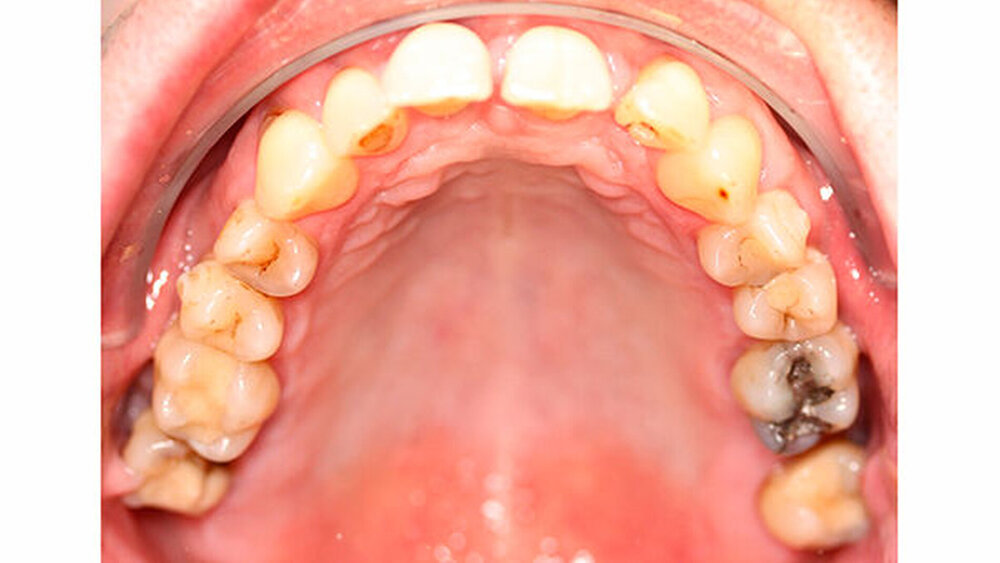

Die Sulkustiefen konnten auf etwas weniger als 4 mm reduziert werden, während der Blutungs- und Plaque-Index bei weniger als 15 Prozent lag. Daher wurde eine kieferorthopädische Behandlung über die nächsten zwei Jahre in Kombination mit engen zahnärztlichen Kontrollen geplant. Als Mittel der Wahl entschieden wir uns gemeinsam mit dem Patienten für das Invisalign-System, da hiermit sowohl eine Schienung als auch eine kraft-arme Bewegung der Zähne möglich sein sollte. Für den Frontzahnbereich wurden keine Attachments geplant, so dass hier eine unnötige Hebelwirkung umgangen werden konnte (Abbildung 3).

Um einen kompletten Lückenschluss im Oberkiefer zu ermöglichen, musste im Unterkieferfrontzahnbereich zusätzlich zur Derotation und Positionierung der Zähne - insbesondere Zahn 41 - von approximaler Schmelzreduktion, kurz ASR , Gebrauch gemacht werden, um einer Tonn`schen Diskrepanz entgegenzuwirken (Abbildung 4).